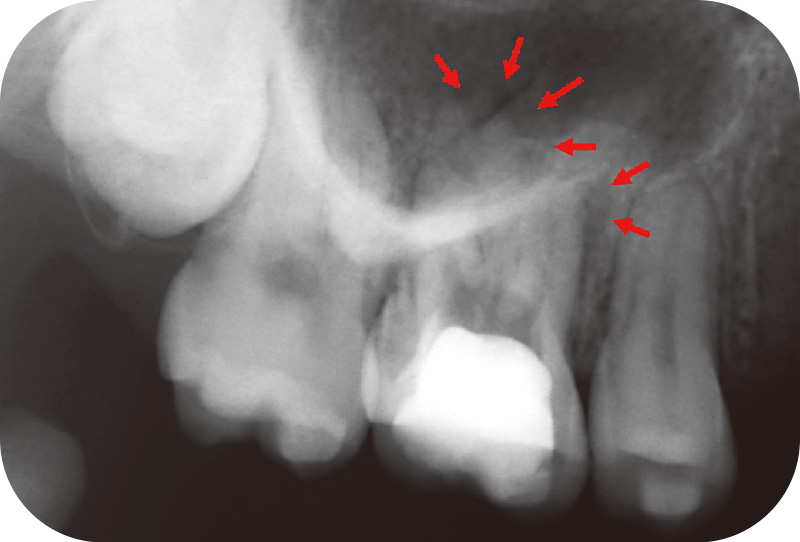

症例1-1 初診時デンタルX線画像。根尖部骨欠損(矢印) -

患者は27歳女性。矯正歯科から根尖病変を指摘され当科を受診した。自覚症状はなかったが、近心頰側根および口蓋根の根尖部に骨欠損を認めた(症例1-1)。CBCTでは両根尖孔の開大と、口蓋根には歯根外部吸収を疑わせる歯質欠損が確認された(症例1-2)。